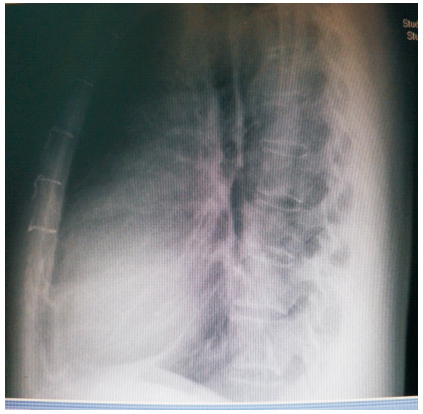

患者59岁,女性,因“发现心脏杂音3个月”于2011年1月份入院。患者2001年因下腔静脉狭窄于外院行下腔静脉支架植入术(支架厂家及型号不详),术后服用培达3个月后停药,无不适。2007年间断出现心悸及胸闷,未诊治。2011年单位体检发现心脏杂音,外院超声提示下腔静脉支架移位至右房,主动脉窦右房瘘。既往:体键。入院查体:血压120/70 mmHg(1 mmHg=0.133 kPa),心律齐,主动脉瓣第一听诊区可闻及Ⅲ/6级收缩期杂音,腹软,无压痛,双下肢不肿。入院诊断:下腔静脉狭窄,下腔静脉支架植入术后,下腔静脉支架移位,主动脉窦右房瘘。入院后相关检查:超声心动图:LV 53 mm,EF 74%,主动脉右冠窦与右房间探及破口约3~4 mm,下腔静脉入右房口处探及支架回声,支架突入右房约20 mm;胸片(图 1、2):侧位片金属支架结构影不连续,心影区偏前区可见线状高密度影。CT(图 3、4):右室游离壁、间隔壁、三尖瓣口、右房、下腔静脉近心段可见支架金属丝影。冠状动脉造影检查(图 5、6):冠状动脉未见明显异常,可见支架影随着心脏的跳动位置发生变化。